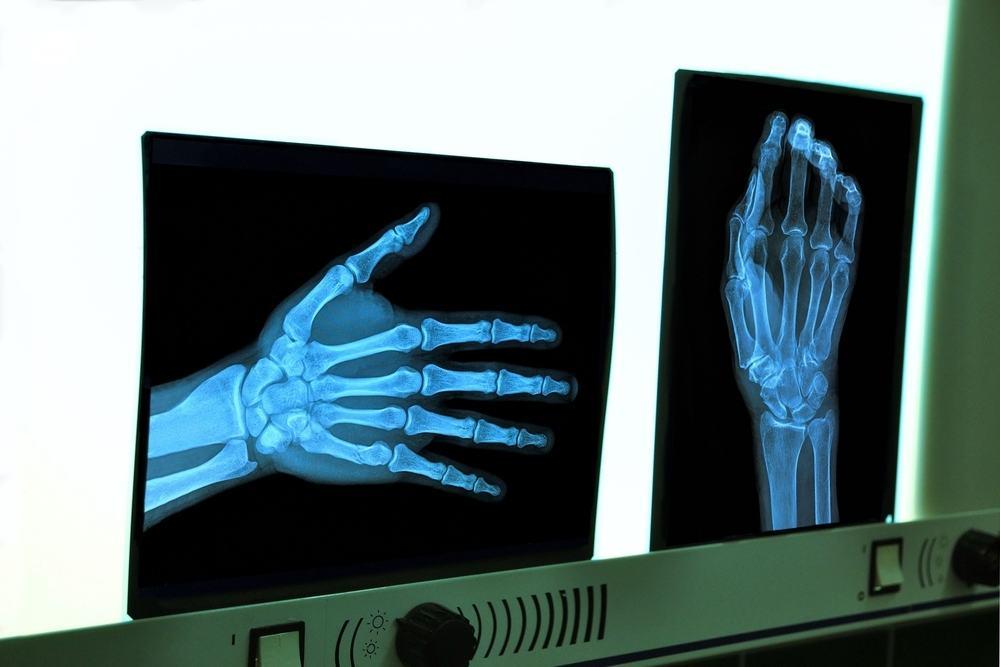

Usia tulang diukur dalam beberapa tahun. Radiografi tangan dan pergelangan tangan adalah cara yang paling umum digunakan untuk menghitung usia tulang.

Cara menghitung umur tulang menggunakan teknik radiografi bisa dilakukan dengan menggunakan alat X-ray di area pergelangan tangan kiri, tangan, dan jari. Tulang seseorang yang terdapat pada gambar X-ray nantinya akan dibandingkan dengan gambar sinar-X dalam atlas standar perkembangan tulang, yang didasarkan pada data dari sejumlah besar tulang orang lain dari jenis kelamin dan usia yang sama.